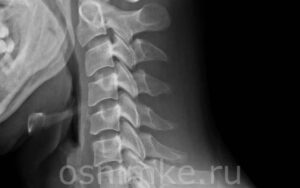

Рентген шейного отдела: что показывает диагностика

Рентгенологическое исследование позвоночника чрезвычайно важно при диагностике заболеваний опорно-двигательного аппарата, нервной и сердечно-сосудистой систем. При обследовании шейного отдела позвоночника это имеет особое значение, поскольку на рентгенограмме шеи выявляются патологии, связанные с головным мозгом, церебральными сосудами. Показания к проведению рентгена Показания к рентгенографии Обследование назначает врач только по показаниям. Рекомендуется обследовать людей с недугами: головные боли; …